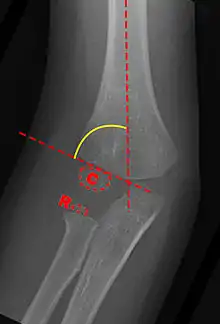

Baumann's Angle

Carrying angle can be evaluated through AP view of the elbow by looking at the Baumann’s angle.[3] There are two definitions of Bowmann's angle:

The first definition of Baumann's angle is an angle between a line parallel to the longitudinal axis of the humeral shaft and a line drawn along the lateral epicondyle.

Another definition of Baumann's angle is also known as the humeral-capitellar angle. It is the angle between the line perpendicular to the long axis of the humerus and the growth plate of the lateral condyle. Reported normal values for Baumann's angle range between 9 and 26°.[7] An angle of more than 10° is regarded as acceptable.[7]